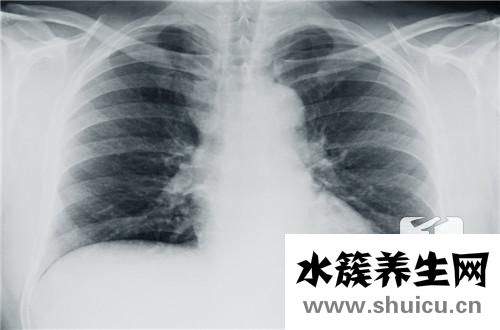

右肋骨下方總是有微弱的疼痛,因此您需要注意了解原因。 常見因素包括長期熬夜,這會導(dǎo)致肝臟超負荷,而肝經(jīng)則會導(dǎo)致右肋骨疼痛和飲食不規(guī)律。 會影響自己。

1、長期熬夜會導(dǎo)致右側(cè)肋骨下疼痛,熬夜對臟器的危害很大,長期熬夜會導(dǎo)致肝臟負擔(dān)過重,肝臟經(jīng)絡(luò)不通,引起經(jīng)絡(luò)停淤,可致右側(cè)肋骨下疼痛。

2、飲食不規(guī)律會導(dǎo)致右側(cè)肋骨下疼痛,這類人群應(yīng)當(dāng)警惕脂肪肝和膽囊炎的發(fā)生,脂肪肝患者一旦出現(xiàn)右側(cè)肋骨下方疼,往往可能已經(jīng)發(fā)展到了中重度,肝臟脂肪變性壞死,損傷嚴重,出現(xiàn)右側(cè)肋骨下疼痛。

3、都市綜合癥、壓力大、心情不好等也會導(dǎo)致右側(cè)肋骨下疼痛,中醫(yī)說:肝為風(fēng)木之臟,其性喜調(diào)達,惡抑郁,如遇情志郁結(jié),肝氣失于疏泄,絡(luò)脈受阻,經(jīng)氣運行不暢,均可發(fā)為脅痛。

4、最常見的就是慢性肝病導(dǎo)致的右側(cè)肋骨下疼痛,慢性肝病病情急性發(fā)作,遷延期轉(zhuǎn)活動期,肝臟細胞損傷加重,肝臟炎癥越來越明顯,常出現(xiàn)右側(cè)肋下陣痛。出現(xiàn)右側(cè)肋骨下方疼不容忽視,建議去正規(guī)的醫(yī)院全面的檢查,明確病因。特別對乙肝病毒攜帶者來說,一旦有右側(cè)肋骨下疼的癥狀出現(xiàn),很有可能病情已經(jīng)惡化到非常嚴重的地步了,必須盡快治療。